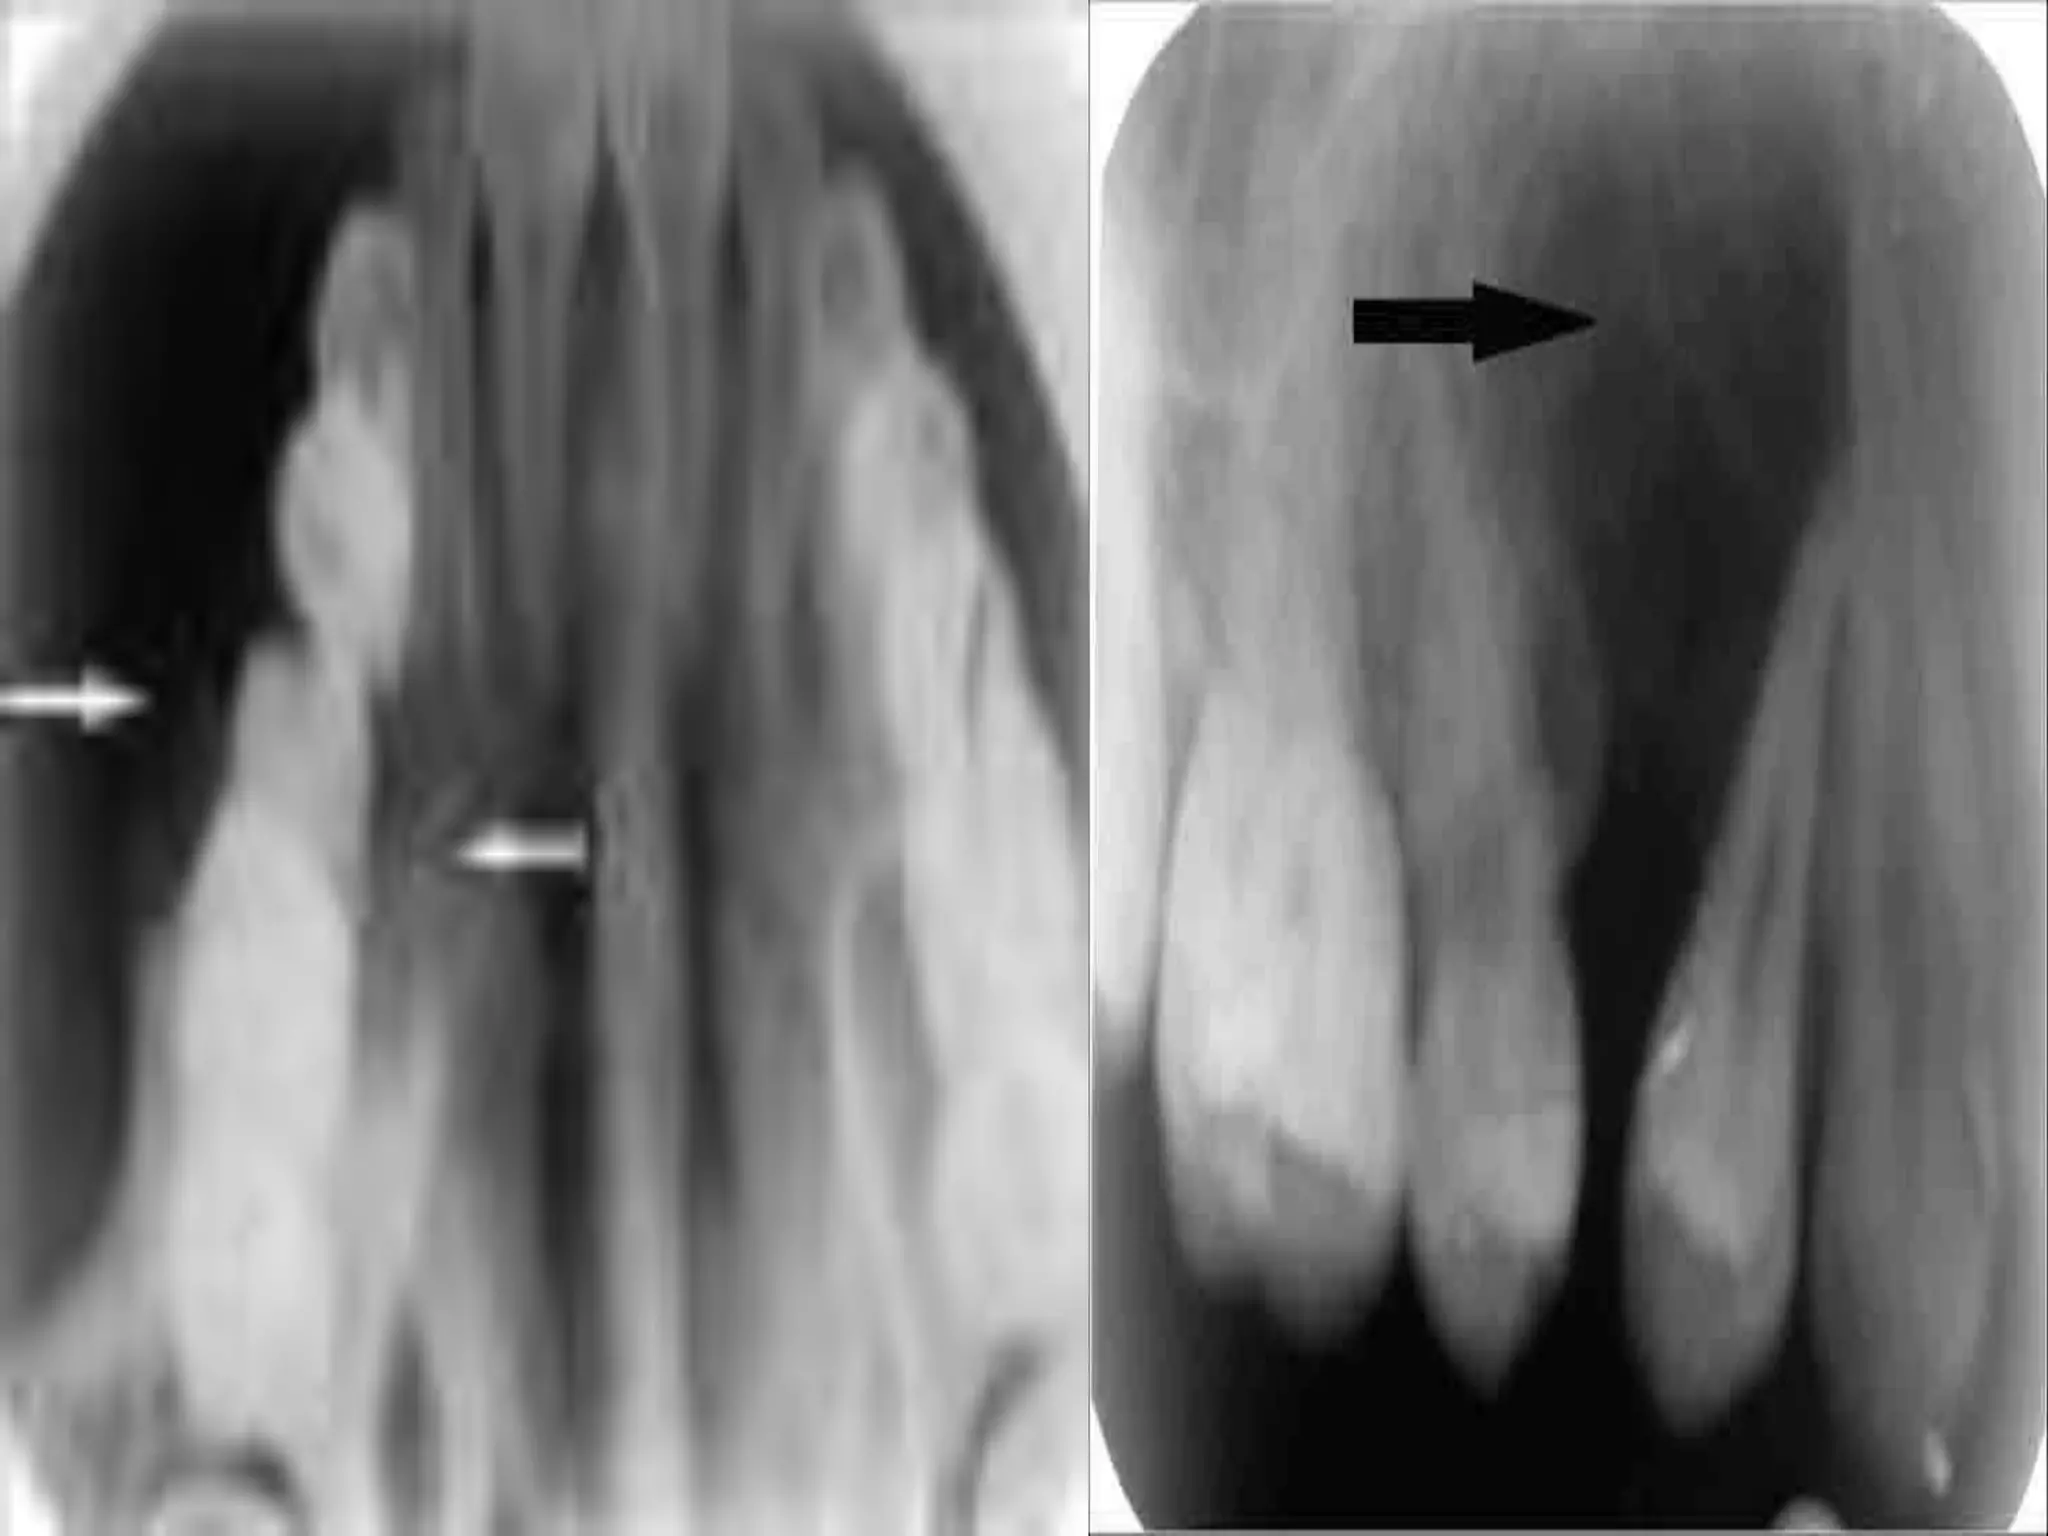

• #19 Intra oral view of buccal aspect with arrows showing anterior and inferior margins of the swelling

• #20 Golg named these spherical structures as ‘psammoma- like bodies’. These particles vary in appearance such a concentric lamellated to irregular both having central basophilic area and a peripheral eosinophilic fringe. Ultra structure of psammoma- like bodies manifest with a dark rim of crystals. From these crystals spicules and needle-like crystalloids project toward the periphery resembling brush border

• #24 JUVENILE Occlusal radiograph marked with arrows showing buccal palatal extension of lesion with ossifications Intraoral periapical radiograph showing mixed radiodensity marked with an arrow, 14, 15 teeth show root divergence